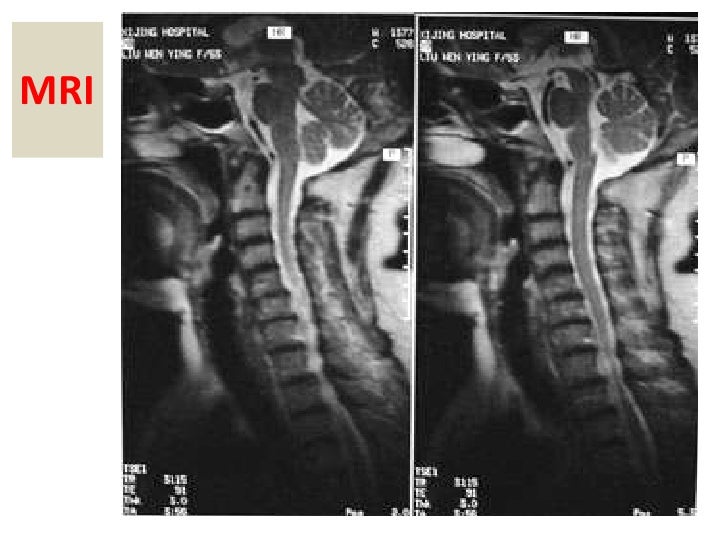

From www.slideshare.net

Cervical Spondylosis Syndrome Arthritis In Neck Cause Vertigo It can also be associated with. Cervical spondylosis is also called cervical osteoarthritis. Cervicogenic dizziness is a condition in which you experience both neck pain and dizziness. It is a condition involving changes to the bones, disks, and joints of. Arthritis, surgery, and trauma to the neck can also block blood flow to these important regions, resulting in this type. Arthritis In Neck Cause Vertigo.